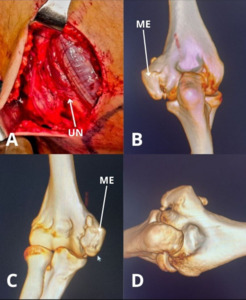

On top of that, when these symptoms occur at rest and together with crepitus, it could even imply the presence of a low-grade synovitis, fractures or degeneration of the joint.7,19 The ulnar nerve could be palpated at the posterior side of the medial epicondyle.20 Figure 1 shows an intraoperative image of the ulnar nerve during an arthroscopic arthrolysis procedure, including additional pre-operative 3D CT reconstructions of the same case. Another way to distinguish the difference in cause of motion restriction is the feel of resistance at passive joint movement. When the endpoint feels firm, it may suggest a mechanical block like osteophyte formation, heterotopic ossification or dislocation.21 Heterotopic ossification would most likely be present alongside local swelling, tenderness and warmth. On the other hand, when it feels more elastic it could be indicative of soft tissue involvement like capsular fibrosis or adhesions.21

The classification system of heterotrophic ossification that would aid in treatment planning is represented by three classes, ranging from asymptomatic findings with heterotrophic ossification to complete ankylosis with or without ulnohumeral/forearm motion.22 The American Shoulder and Elbow Surgeons (ASES) also introduced standardized assessment guidelines to evaluate elbow function.23 Regarding imaging, the standard included anteroposterior and lateral radiographs.1,7,8 On the contrary, the use of computed tomography (CT) imaging would be superior when the contractures exceed 30 degrees or heterotrophic bone is present, as well as when physeal injury is suspected in skeletally immature patients or children.1,7,8 Ultrasound or electroneuromyography could be helpful to evaluate the ulnar nerve. Magnetic Resonance Imaging (MRI) is rarely used but may be reserved for the evaluation of inflammatory causes or soft tissue pathologies.1,7,8 In the child and adolescent, MRI is more often used as an accessory imaging modality to reliably measure the angle of the trochlear notch. Imaging modalities like MRI and 3D CT reconstructions are crucial when assessing joint morphology, bony impingement, or avascular necrosis, for which an example case is shown in Figure 2.